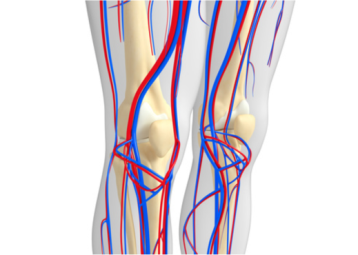

La patología vascular, esa amplia categoría de enfermedades que abarca los trastornos de los vasos sanguíneos, ya sean arterias o venas, es motivo de profunda preocupación en el ámbito…